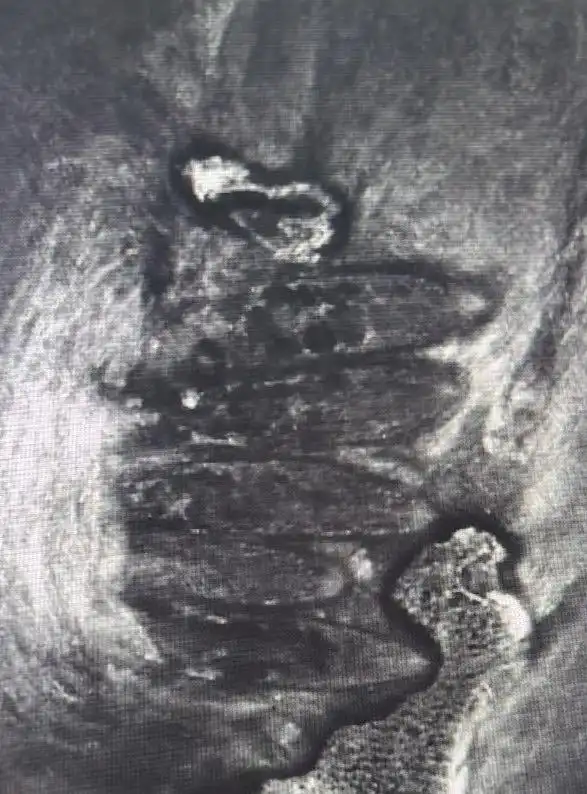

經(jīng)共聚焦顯微鏡檢測(cè),醫(yī)生在小浩雙眼18個(gè)毛囊中揪出86只蠕形螨,右眼39只、左眼47只的檢測(cè)結(jié)果讓醫(yī)護(hù)人員直呼罕見。“這簡(jiǎn)直就是螨蟲在眼睛里安了家!”主刀醫(yī)生鄧軍表示,小浩長(zhǎng)期嗜好油炸食品、甜食,青春期油脂分泌旺盛,為螨蟲提供了絕佳生存環(huán)境。